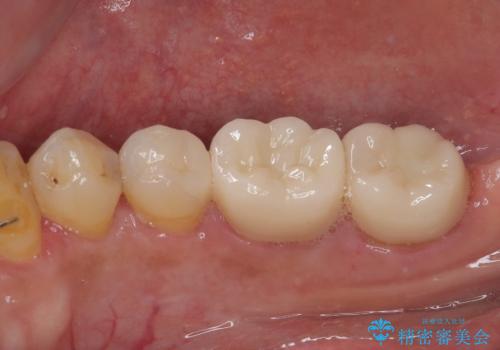

根管治療後痛みもなくなり快適に使っていただけています。

順次残っている銀歯も虫歯治療を行いながらセラミックに置き換えていく予定です。